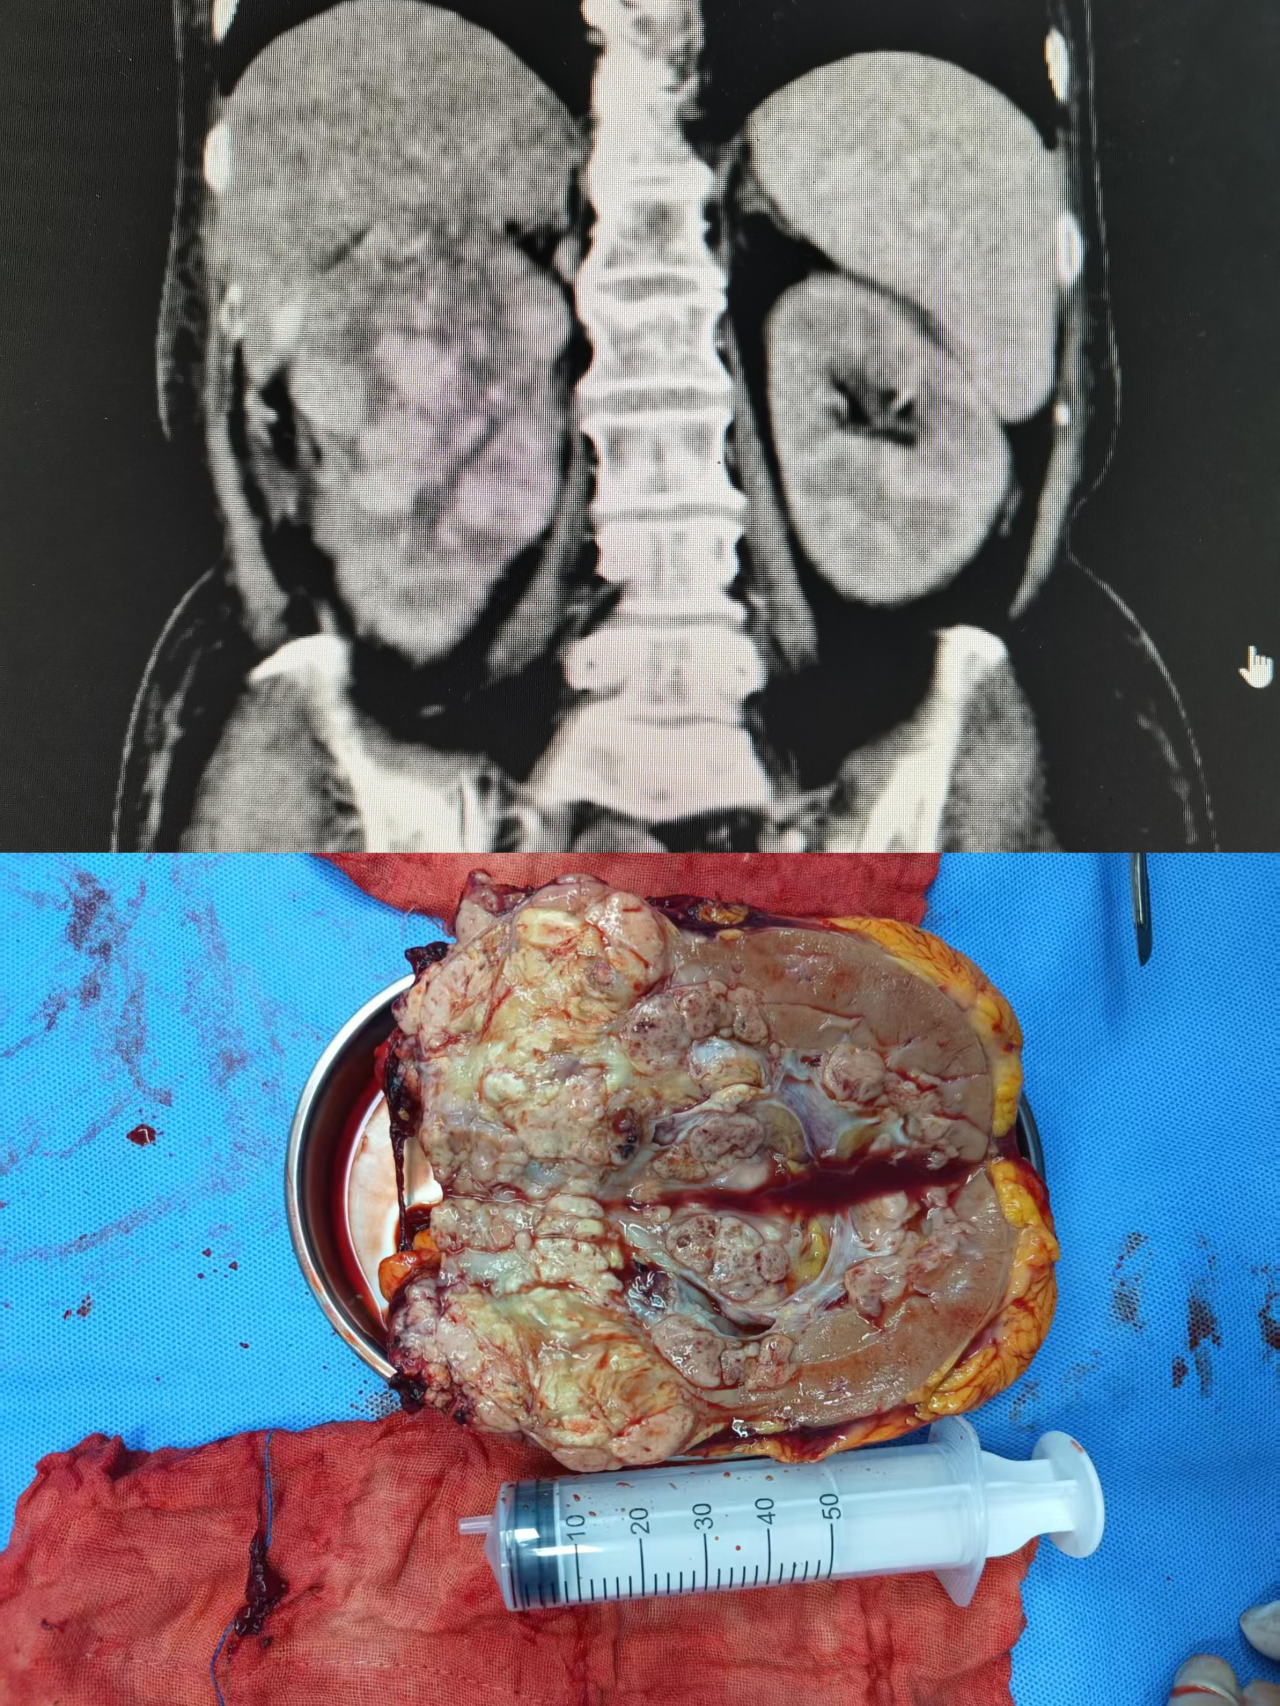

转入泌尿外科后,肖峰主任团队在王阿姨术前血红蛋白仅有65g/L的情况下,经过输血支持,成功为她实施了右肾肿瘤切除手术。手术历时两小时,术后,王阿姨贫血相关症状得到根本性纠正,再也不需要靠输血度日。